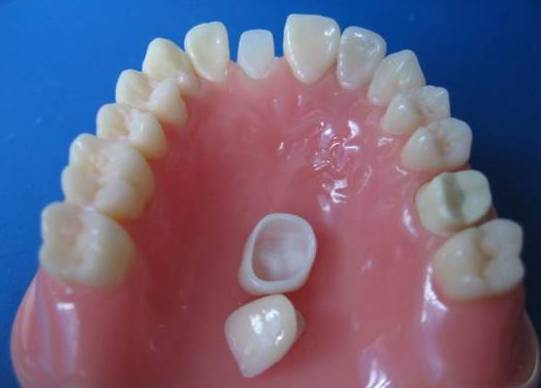

01.二氧化锆的特性

1、颜色与天然牙色泽非常相似,拥有高度的美学效果,优良的透光性、更适合在美观性要求高的部位使用。

2、口腔中没有金属异味,不腐蚀、不因冷热的交替而刺激牙髓神经,出色的生物相容性,持久耐用。能经受搞强度的咬合力,防止折裂,坚固耐用。解决了金属烤瓷牙龈透青,黑线和变色问题。

3、核磁共振检查时,非金属的氧化锆对X线无任何阻挡,核磁共振检查时都不需要拆掉假牙,省去很多麻烦。

03.预备基牙的要求

1、前牙

切端磨除约2.0毫米,舌侧磨除约1.5毫米预备360度,宽约1毫米的肩台,轴向颌角2度-5度;

2、后牙

颌面磨除约2.0毫米(工作侧2.0毫米,非工作侧约1.5毫米),颊舌侧磨除1.5毫米预备360度,宽约1.0毫米的肩台,轴向颌角2度-5度;

3、贴面

制备定位在牙釉质部分关键是舌侧切缘处要有一个过渡的台阶,并确定台阶的边缘不是在咬颌的磨损区域,切端制备的范围大约在1--1.5毫米,唇面约1.2--1.5毫米,牙颈部分的肩台制备角大约在10度--30度。